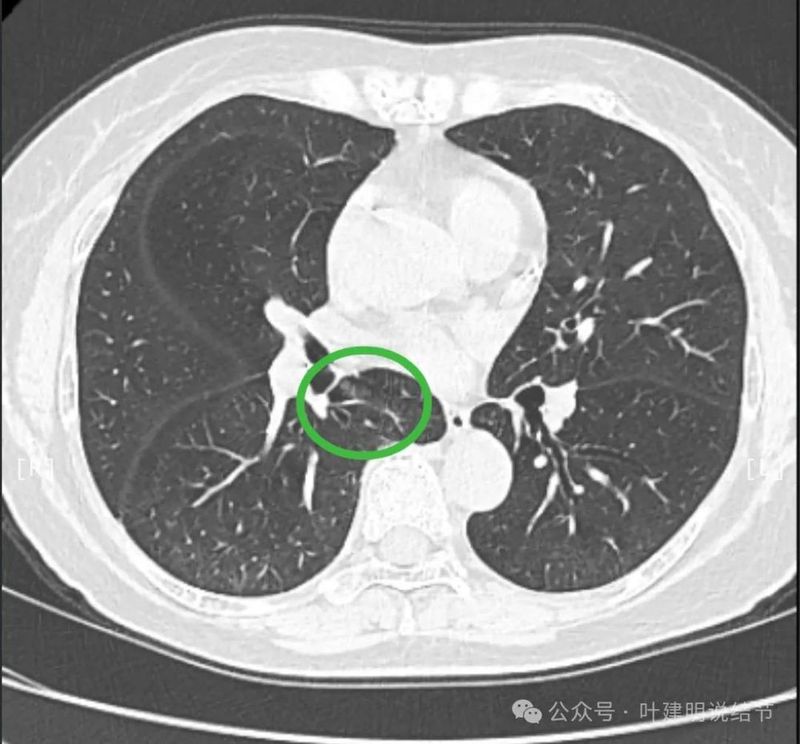

先看患者提供的2024年2月份的CT影像:

病灶出现,在右下叶支气管旁边,轮廓清楚,此层似磨玻璃密度。

表面似分叶状,密度不纯,邻近血管略有弯曲向病灶。

实性密度,边缘光滑,与背段支气管亚段贴着。